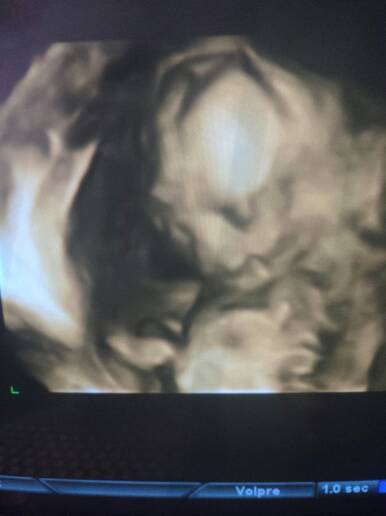

今天去检查的,看图片能看出宝宝是不是兔唇,为什么看他像兔唇呢,大夫说宝宝挺健康,今天正好十七周,会看的帮我看看吧

你好。照片上看不清楚的,超声会提示胎儿上唇线连续不连续或完整不完整,如果是连续的,完整的,就不是兔唇。

没有超声结果单,即使这样,如果有问题,医生肯定会告诉你的,或者让你复查什么的。 之前肯定也有超声检查吧,也没有说过有问题, 以后还会有超声检查的,有问题的话一般也会发现的。